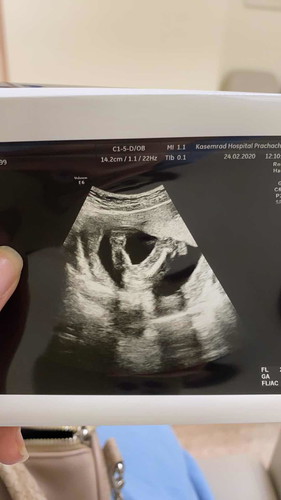

แม่ๆช่วยดูหน่อยค่ะ แบบนี้เป็น ผญ ใช่มั้ยคะ หมอบอกไม่มีจู๋โผล่ออกมา ตอนนี้อายุครรภ์ 18weeks ค่ะ จะมีแบบ แอบไว้มั้ยคะ ?